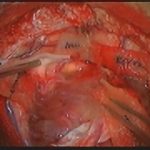

手術前1

摘出 前